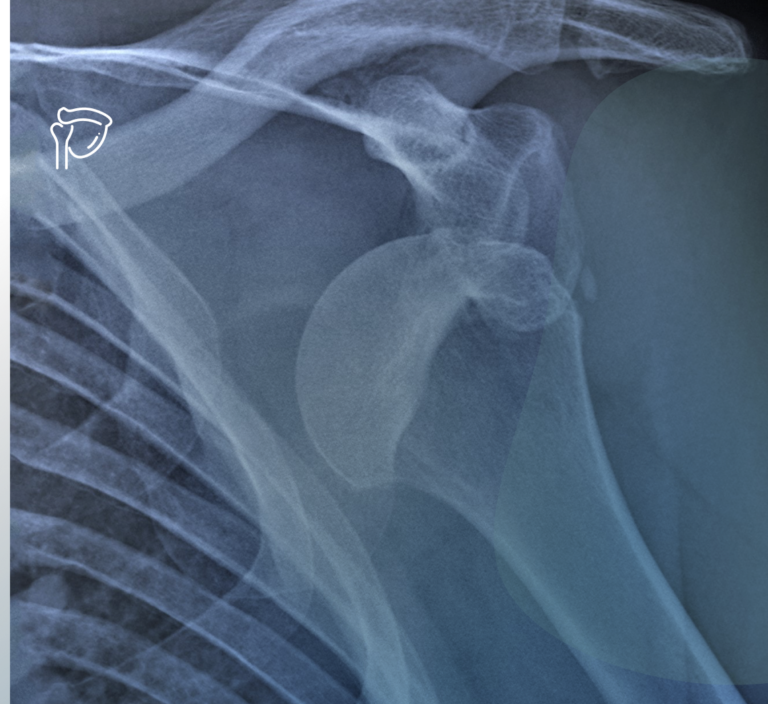

Lussazione di spalla. Quali solo le conseguenze più comuni